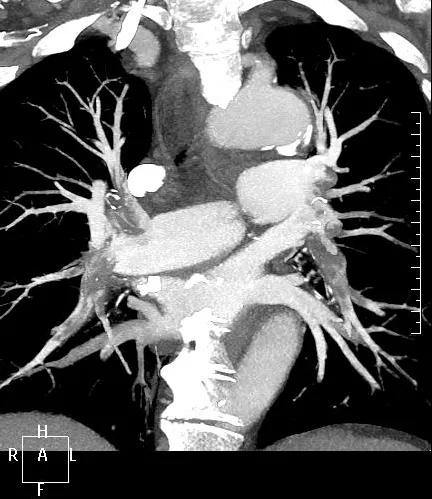

近日,一名港胞翁阿姨在我市突發(fā)急性肺栓塞,生命垂危。市二院在接到120出車(chē)指令后,迅速響應(yīng),患者入院后開(kāi)通綠色通道,經(jīng)急診科、心內(nèi)科、介入科、重癥醫(yī)學(xué)科等多學(xué)科專(zhuān)家開(kāi)展聯(lián)合會(huì)診,并于當(dāng)晚9點(diǎn)行“下腔靜脈、肺動(dòng)脈造影+導(dǎo)管溶栓+濾器植入術(shù)”,患者終于轉(zhuǎn)危為安,經(jīng)后續(xù)治療與精心護(hù)理,病情逐漸穩(wěn)定,現(xiàn)已轉(zhuǎn)入普通病房。